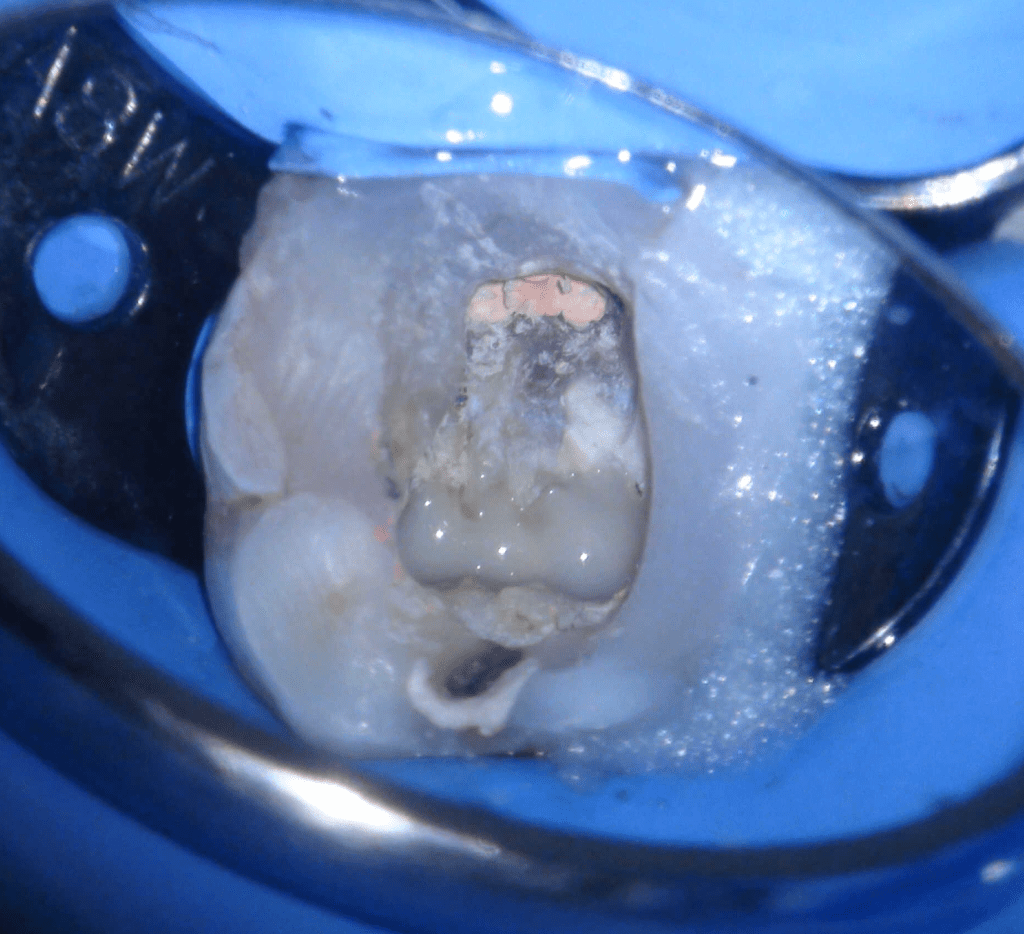

Reco preendo + 4 conductos molar superior